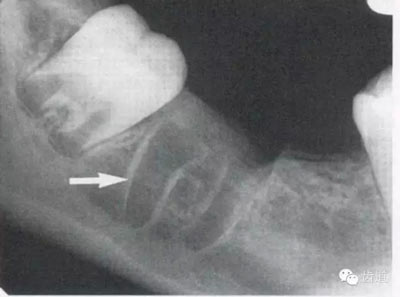

4)外斜線:

由升支前緣下部斜向前下方,為一密度高的帶狀影像。常重疊在第二、三磨牙牙冠處、頸部或根部,使牙髓室或根管不能清晰顯示

5)下頜管:

位于磨牙牙根尖下方,呈寬約為0.4cm凹面向下邊緣整齊的帶狀密度低的影像,其兩側(cè)有密度高的線條狀影像,為下頜管骨密質(zhì)